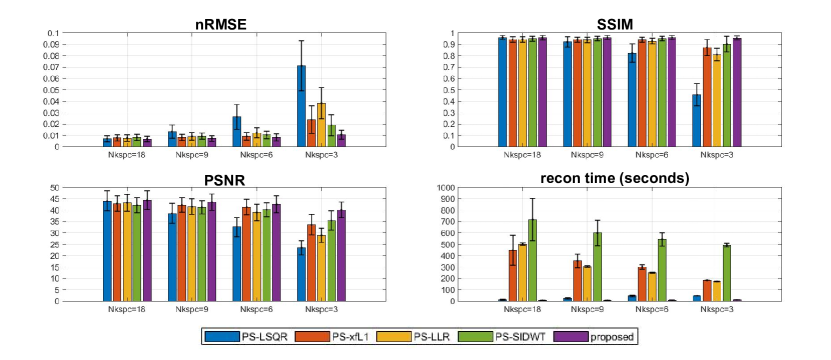

4.3.1 Comparative Study on Nkspc

The quality of PS model reconstruction is dependent on the total amount of “Imaging data”. More “Imaging data” leads to higher reconstruction quality, while at the expense of longer acquisition time. In this study, we use Nkspc to quantify the “Imaging data” amount, which denotes the number of full k-space if we neglect the phase encoding position and collect all the “Imaging data” compactly. Compared with total acquisition time, Nkspc is a better measurement of the difficulty for solving a PS model problem, because Nkspc is irrelevant of sequence TR, scan resolution, spatial coverage, and many other practical factors. Reconstruction experiments were performed on the retrospective dataset under Nkspc=18, 9, 6, 3. Quality metrics of nRMSE(normalized root mean square error), PSNR(peak signal to noise ratio), SSIM(structural similarity) were calculated based on the fully-sampled reference image, and the reconstruction time was recorded.

5.2.1 Comparative Study on Nkspc

The reconstructed images for different Nkspc settings are shown in Figure 4. Under Nkspc=18, all the models produce similarly high quality images, with nRMSE slightly above 0.01, PSNR above 38 and SSIM above 0.90. When Nkspc is reduced to 9 and 6, the image quality of PS-LSQR model deteriorates obviously, while the performance of the other algorithms are only slightly affected. When the Nkspc is further reduced to 3, a notable image quality decline can be observed for the PS-xfL1, PS-LLR and PS-SIDWT methods. Only the proposed method can still keep good visual image quality. This suggests that the proposed method is the most stable algorithm when the acquisition time is significantly shortened. Besides, it can be observed that the operator optimization significantly reduces the computation time for all algorithms. The acceleration factor increases with the Nkspc value, which means more reconstruction time can be saved if the acquisition time is prolonged. For all Nkspc settings, the proposed method is always the fastest algorithm.

The statistical results on the retrospective dataset are shown in Figure 5. The proposed method usually achieves the lowest average nRMSE, the highest average PSNR and SSIM. Moreover, the proposed method also shows the lowest standard deviation (std) nearly among all metrics, which implies that the proposed method has high robustness among different data cases. Additionally, the advantage of the proposed method in reconstruction speed is very prominent. In short, the proposed method achieves the best image quality and the fastest speed on the dataset, and is robust against shortened acquisition time.